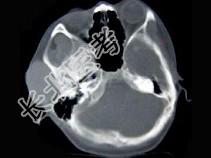

- 单项选择题女,19岁, 右侧面颊部肿胀1年,CT检查如图所示, 最可能的诊断是 ( )